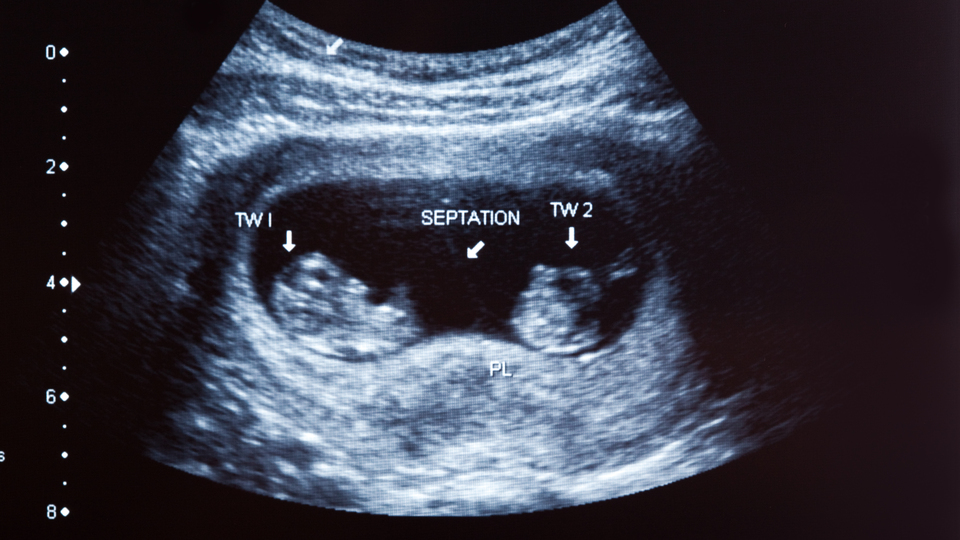

ULTRASON YÖNTEMİYLE GÖZLEMLENEBİLİR

Gebeliğin teşhisinde kullanılan ultrason yönteminin yaygınlaşmasından sonra kaybolan ikizleri teşhis etmenin daha kolay olduğunu belirten Op. Dr. Ağır, "Hamilelik süreçlerinin ilk üç aylık döneminde ikiz veya çoklu fetüsler tespit edilebilmektedir. Bu nedenle fetüslerde bir değişiklik olup olmadığı ultrasonla gözlemlenebilmektedir. İkiz bebeklere sahip olan anne adayları, hamile olduklarını öğrendikten sonra gerçekleşen kontrollerde, eğer ikizlerden biri kaybolmuşsa bu durum rahatlıkla görülebilirler" diye konuştu.